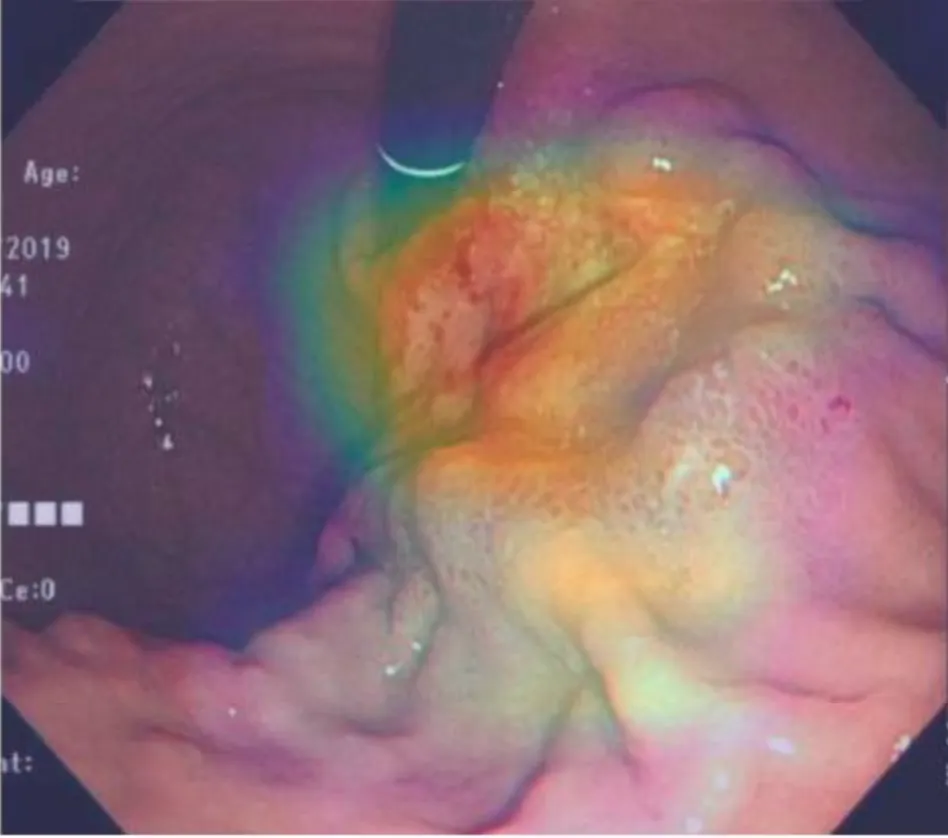

6.6.虚拟电子染色:使用稳定扩散(SD)实现内镜中白光图像—虚拟电子染色(Vir-NBI)图像的转变,可以生成具有高度细节和真实性的图像